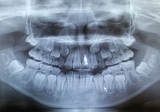

レントゲン検査の役割: レントゲン撮影は虫歯の進行具合を評価するために重要な手法です。レントゲン画像を通じて、歯の内部の虫歯の進行状況や根の状態を見ることができます。